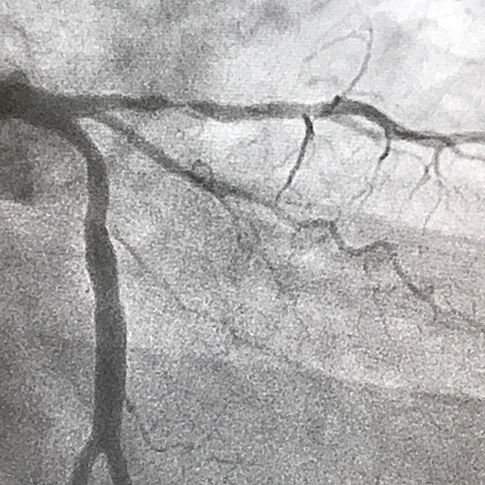

Girişimsel Kardiyoloji

Kalp Damar Hastalıklarının Öncesi Sonrası